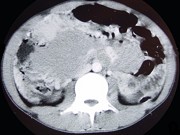

- 单项选择题男,22岁, 下腹部包块,1个月, 伴低热乏力,浅表淋巴结肿大, 影像检查如图,最可能诊断为 ( )

C、肠淋巴瘤